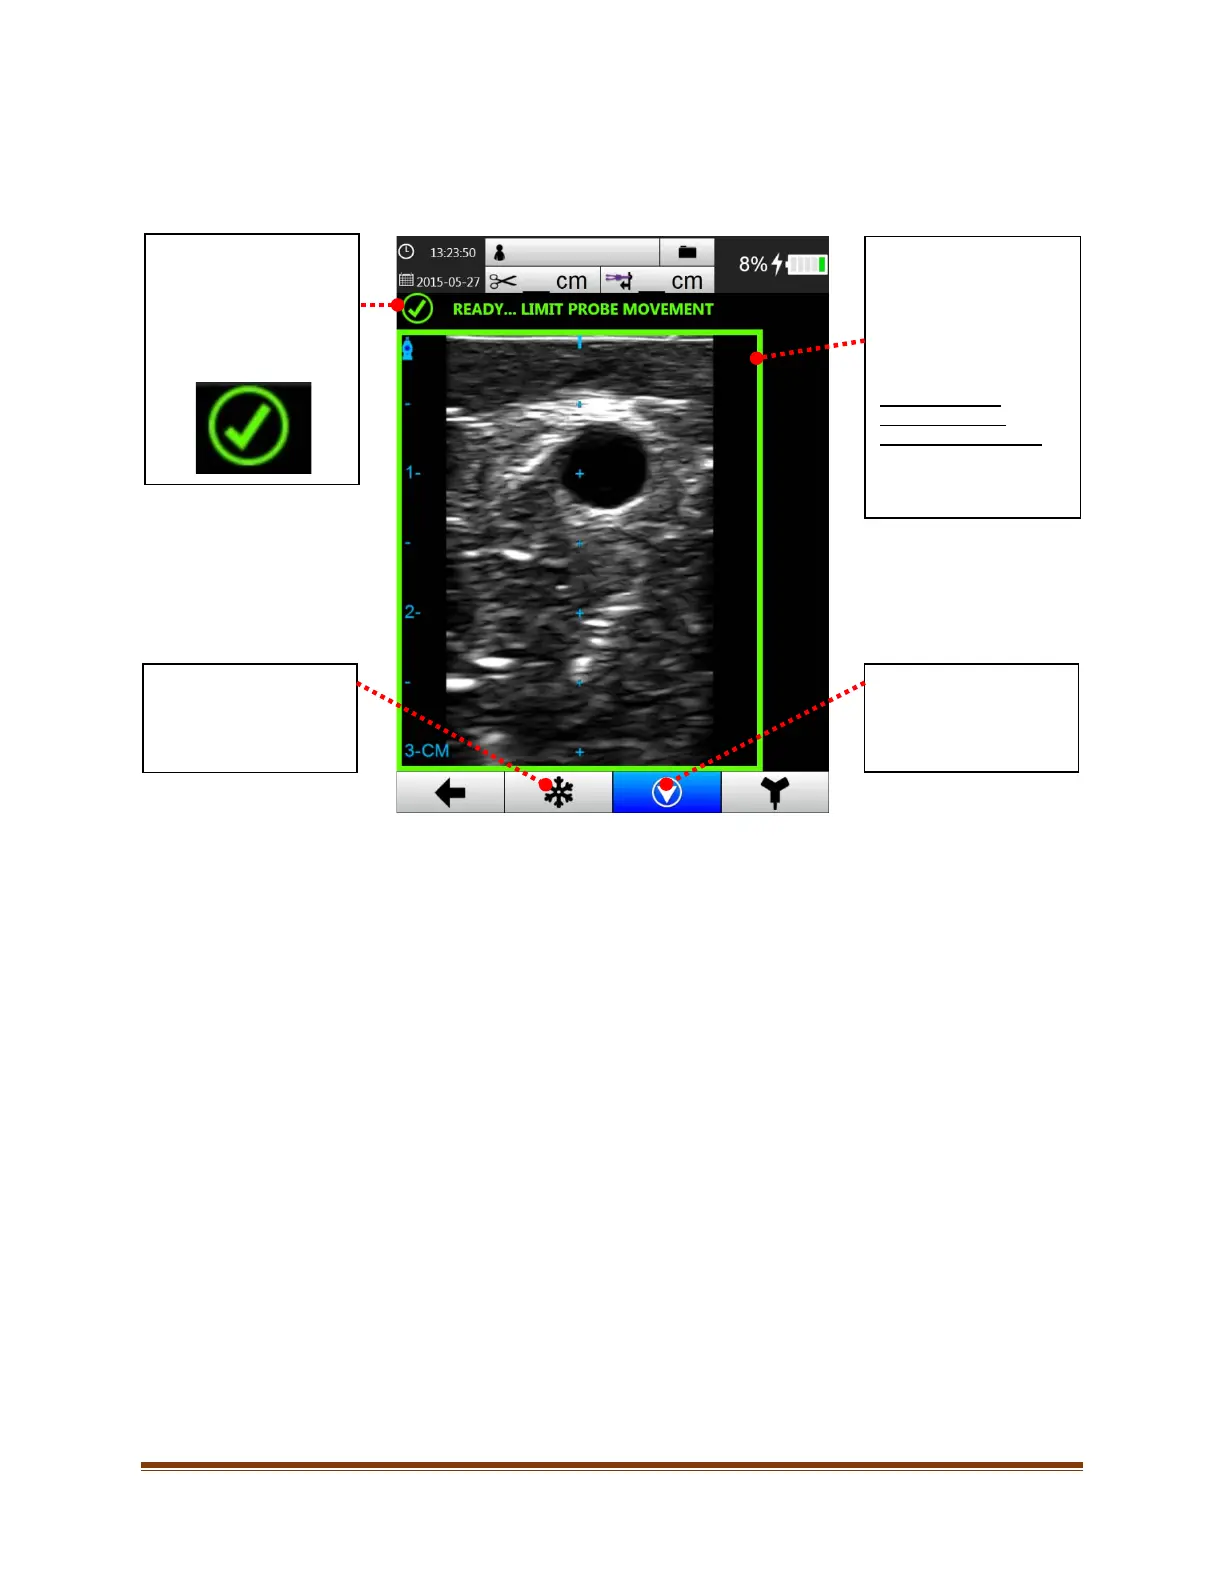

10.3. PinpointGT Needle Technology Needle Tracking

Once PinpointGT Needle Technology has finished calibrating, the system is ready to begin tracking PinpointGT

Needle Technology compatible needles.

Calibration Status Icon

Once Pinpoint™ GT

Needle Technology is

calibrated, the status icon

will change to a green

check mark.

Freeze Button

After calibration has

completed, the freeze

button is accessible.

Calibration Status

Border

This border indicates the

calibration status of

Pinpoint™ GT Needle

Technology.

Green Border

“READY… LIMIT

PROBE MOVEMENT”

System is calibrated and

ready for needle tracking.

Calibrate Button

completed, the calibrate